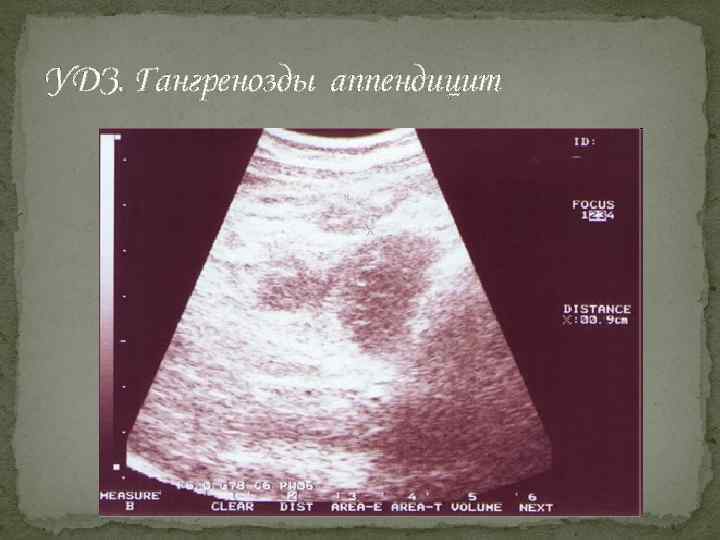

УДЗ. Гангренозды аппендицит

Инструменталдық әдістер Ø Шолу рентгенографияда оң жақ мықын аймағында үрленген ішекті немесе рентгенконтрасты нәжіс тастарын көруге болады. Ø Лапароскопияда қабынған құрттәрізді өсіндіне немесе қабынудың қосымша көріністерін табуға болады. Ø УДЗ жуандаған, ісінген құрттәрізді өсіндіні анықтайды. Ø Аппендэктомия Ø Компьютерлі томография